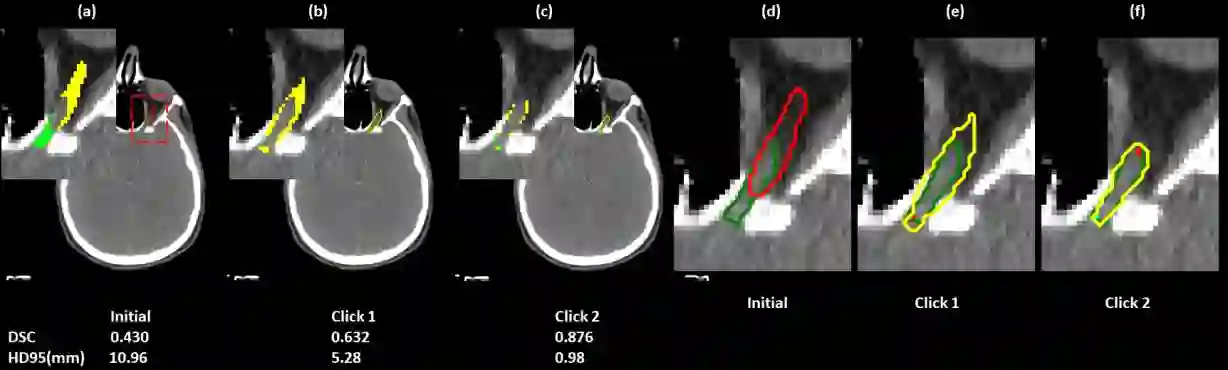

Automatic segmentation of anatomical structures is critical for many medical applications. However, the results are not always clinically acceptable and require tedious manual revision. Here, we present a novel concept called artificial intelligence assisted contour revision (AIACR) and demonstrate its feasibility. The proposed clinical workflow of AIACR is as follows given an initial contour that requires a clinicians revision, the clinician indicates where a large revision is needed, and a trained deep learning (DL) model takes this input to update the contour. This process repeats until a clinically acceptable contour is achieved. The DL model is designed to minimize the clinicians input at each iteration and to minimize the number of iterations needed to reach acceptance. In this proof-of-concept study, we demonstrated the concept on 2D axial images of three head-and-neck cancer datasets, with the clinicians input at each iteration being one mouse click on the desired location of the contour segment. The performance of the model is quantified with Dice Similarity Coefficient (DSC) and 95th percentile of Hausdorff Distance (HD95). The average DSC/HD95 (mm) of the auto-generated initial contours were 0.82/4.3, 0.73/5.6 and 0.67/11.4 for three datasets, which were improved to 0.91/2.1, 0.86/2.4 and 0.86/4.7 with three mouse clicks, respectively. Each DL-based contour update requires around 20 ms. We proposed a novel AIACR concept that uses DL models to assist clinicians in revising contours in an efficient and effective way, and we demonstrated its feasibility by using 2D axial CT images from three head-and-neck cancer datasets.